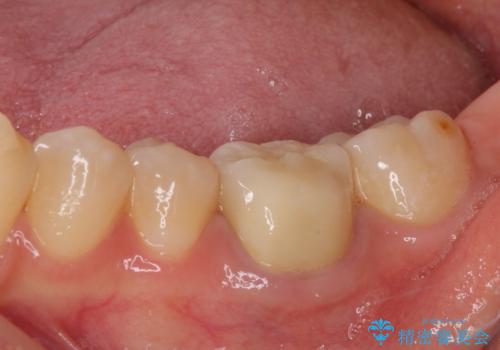

矯正治療後は上顎前歯4本をオールセラミッククラウンにて補綴治療を行うこととしました。

むし歯が多かったため、ワイヤー矯正中に処置したむし歯が悪化することが懸念されましたが、歯磨きをしっかりと行ってくれたため、とても良好な状態を維持することができました。